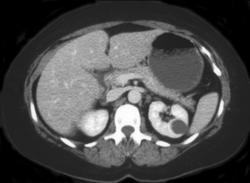

Vascular Renal Cell Carcinoma